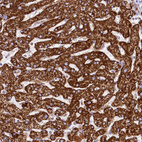

Immunohistochemical staining of human gastrointestinal, kidney, liver and lung using Anti-CLYBL antibody HPA040691 (A) shows similar protein distribution across tissues to independent antibody HPA039959 (B).